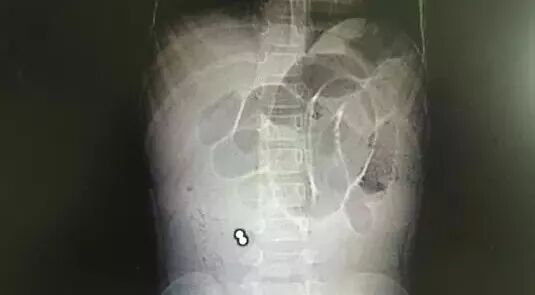

溫溫在惠州市第三人民醫(yī)院門診拍了胸片,提示:兩個高密度影,伴有腸梗阻表現(xiàn)。

如片子所示,患者右下腹可見兩個圓圓的小球,顏色越白,說明物體的密度越高,高度懷疑是小鐵球之類的東西。這兩個小球是腸梗阻的罪魁禍首嗎?

后來溫溫做了個CT,高度提示是消化道異物、腸梗阻及包裹。反復詢問小姑娘及其父母,都否認吞服過異物。這兩個小球緊緊地挨在一起,莫非……